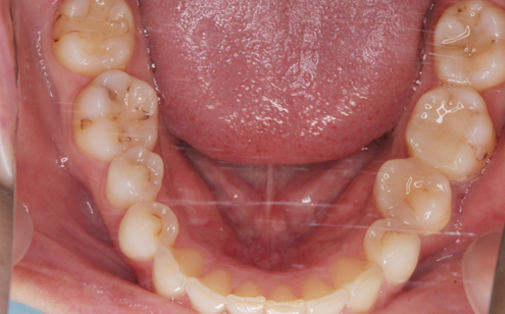

抜歯した親知らずを移植(2)

Before

After

左下の親知らずの歯を移植の症例です。